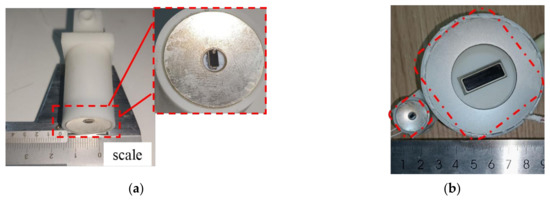

The integrated probe prototype is depicted in Figure 1a, which displays a single-element imaging probe positioned within the central hole of a spherical-focused therapeutic probe. The therapeutic probe operates at a center frequency of 4.5 MHz, while the imaging probe operates at 12 MHz. Two probes were fixed to the mechanical structure by connectors. Compared to the therapy system guided by a linear array B-mode imaging probe, the volume is significantly reduced, which is depicted in Figure 1b.

Figure 1.

Prototype probe for integrated ultrasound imaging and therapy: (a) system guided by a single-element imaging probe; (b) dimensional comparison, the right is a system guided by a B-mode imaging probe.